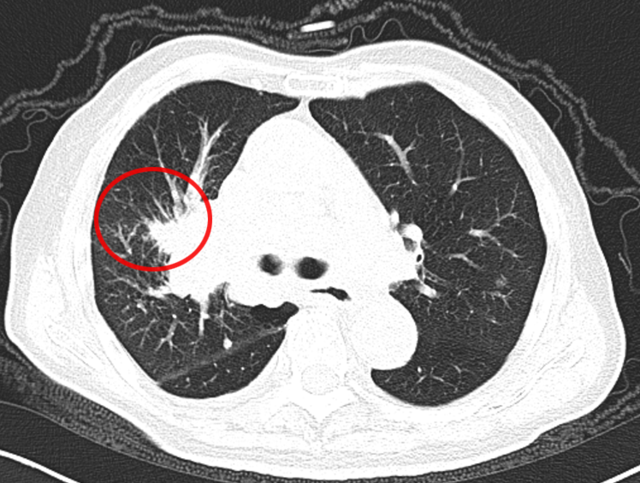

临床上曾遇到一位 80 岁的老先生,1 年多前做过结肠癌手术,病理提示为 “低分化腺癌”,术后也完成了辅助化疗。近期复查 CT 时,医生发现他的右肺门长了新东西!

从 CT 影像看,这个右肺门肿块高度怀疑是恶性肿瘤。但问题来了:老先生有结肠癌病史,这个肺肿块是新长的肺癌(原住民),还是结肠癌转移到肺部(移民者) ?

要知道,这两种情况的治疗方案截然不同,必须先明确 “肿瘤君的身份”。

起初,常规思路是做气管镜检查取病理,但完善肺功能检查后发现,老先生有重度阻塞性肺通气功能障碍(相当于呼吸系统 “交通堵塞”),根本耐受不了气管镜。好在这个肿块虽然位置特殊,但体积较大、离胸壁较近 —— 和患者及家属充分沟通后,医生决定采用 “CT 引导下经皮肺穿刺活检”。